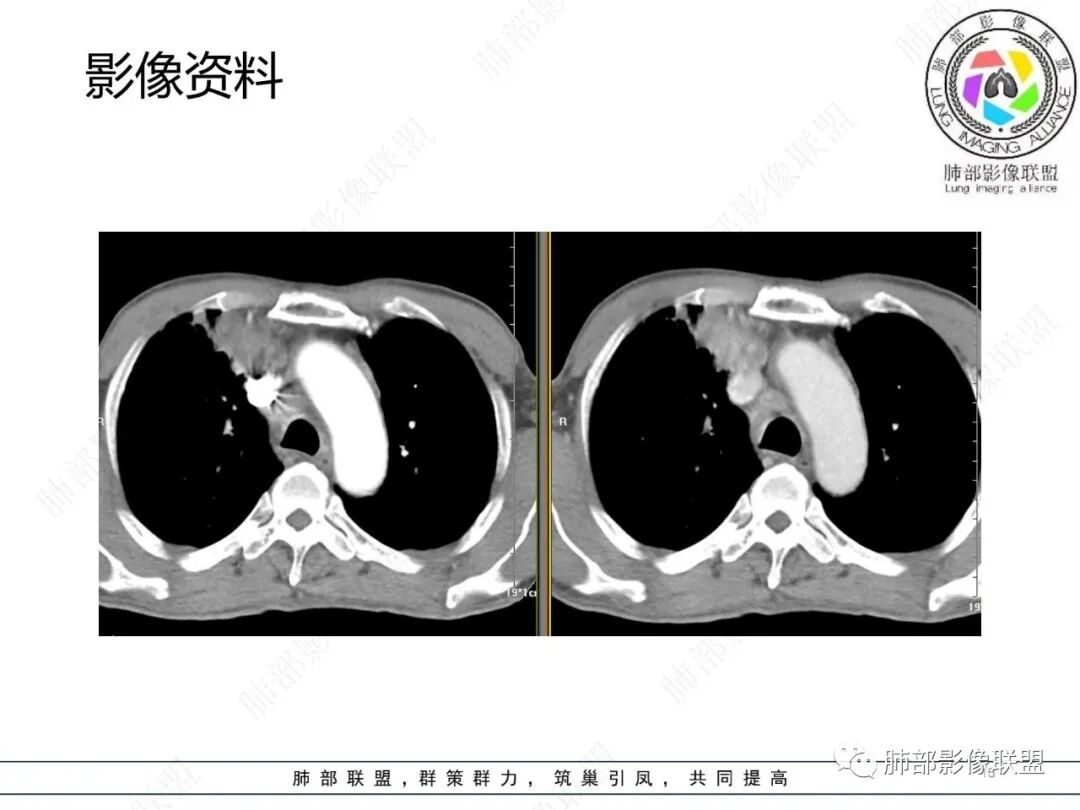

影像资料

2.胸部CT: 右肺病灶,主要累及右肺上叶前段、右肺中叶内侧段及右肺下叶背段,片状影及结节影,实性密度为主,部分磨玻璃晕,密度不均,散在钙化,其中上叶前段支气管闭塞,隐约见钙化突入。未见明确“硬树芽”或“拐枣征”。主要呈延迟强化,其间低密度区疑坏死或粘液成分。纵隔内见多组淋巴结肿大环形强化,部分钙化。